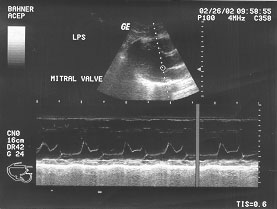

Cardiac - long axis parasternal spectral doppler - mitral valve